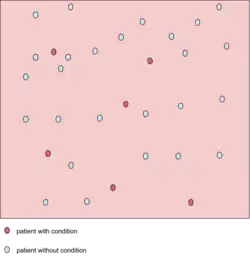

A test result with 100 percent sensitivity

A test result with 100 percent sensitivity -

A test result with 100 percent specificity

A test result with 100 percent specificity

The red dot indicates the patient with the medical condition. The red background indicates the area where the test predicts the data point to be positive. The true positive in this figure is 6, and false negatives of 0 (because all positive condition is correctly predicted as positive). Therefore, the sensitivity is 100% (from 6 / (6 + 0)). This situation is also illustrated in the previous figure where the dotted line is at position A (the left-hand side is predicted as negative by the model, the right-hand side is predicted as positive by the model). When the dotted line, test cut-off line, is at position A, the test correctly predicts all the population of the true positive class, but it will fail to correctly identify the data point from the true negative class.

Similar to the previously explained figure, the red dot indicates the patient with the medical condition. However, in this case, the green background indicates that the test predicts that all patients are free of the medical condition. The number of data point that is true negative is then 26, and the number of false positives is 0. This result in 100% specificity (from 26 / (26 + 0)). Therefore, sensitivity or specificity alone cannot be used to measure the performance of the test.